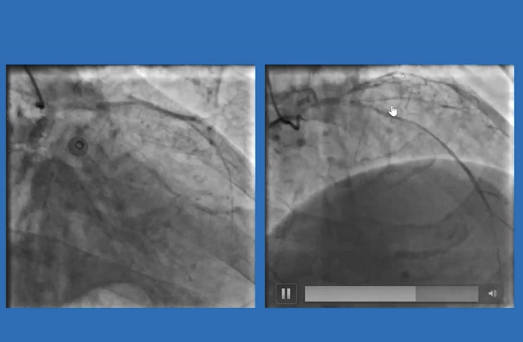

病例二:男性患者,EF值仅 31.8%,既往有搭桥和PCI病史,冠脉造影提示桥血管、LCX、RCA均闭塞,LAD是唯一残存血管,患者及家属拒绝再次搭桥治疗。

遂决定术前在股动脉处预埋两把血管缝合器,在ECMO支持下先对LAD病变进行了血运重建,患者术中血流动力学稳定,术后导管室即刻拔管并缝合血管。一个月后行择期PCI开通RCA闭塞病变。

病例三:78岁男性患者,EF值仅35%,因STEMI急诊入院后行冠脉造影示RCA全程弥漫病变伴钙化,最重处狭窄90%;LM钙化,LAD近段次全闭塞,D1开口狭窄90%;LCX开口完全闭塞;尝试处理LAD病变,但球囊无法通过。

本次入院后对外周动脉进行评估,遂在行PCI时植入ECMO提供血流动力学支持,成功对LAD钙化病变进行了旋磨治疗。术中全程患者生命体征稳定,术后即刻拔除ECMO。